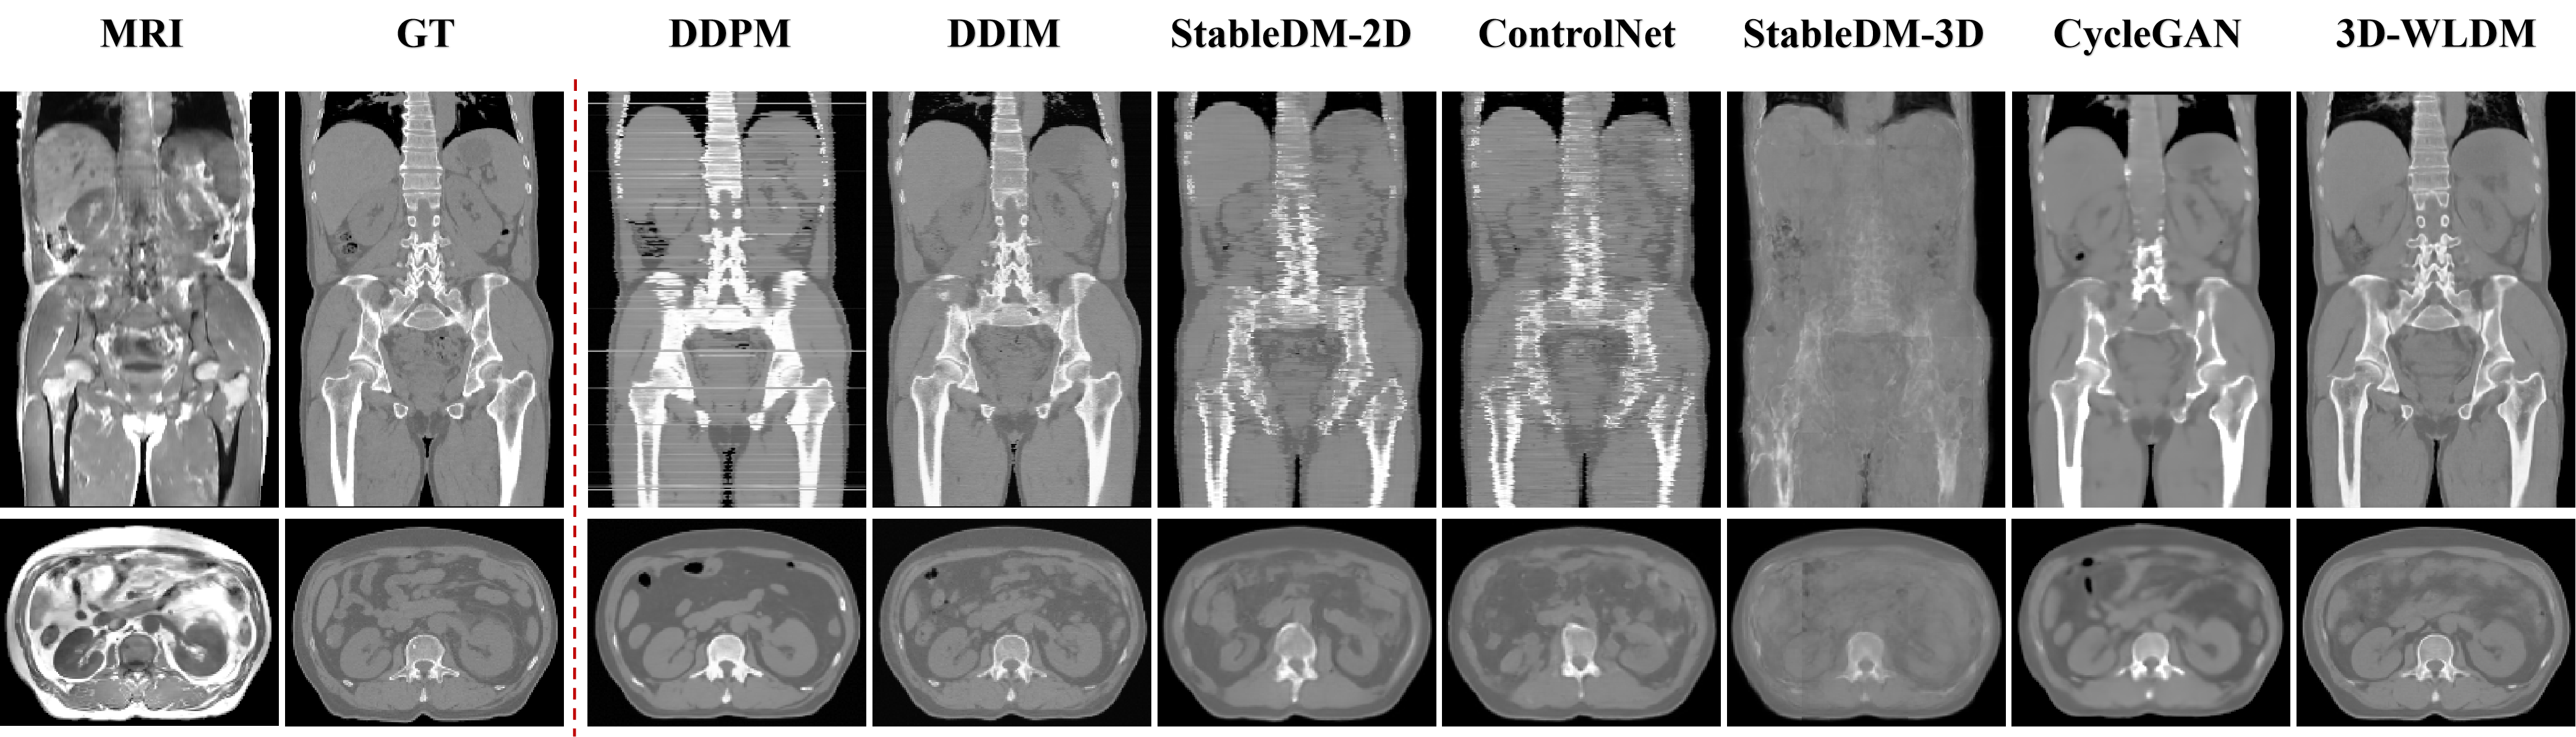

We performed MR-to-CT modality translation experiments to benchmark the proposed 3D Wavelet Latent Diffusion Model (3D-WLDM) against several state-of-the-art baselines, including DDPM [41], DDIM [39], StableDiffusion 2D (StableDM-2D)[37], ControlNet[34], StableDiffusion 3D (StableDM-3D)[37], and CycleGAN[42]. Representative qualitative comparisons are illustrated in Fig. 5.

In 2D transverse slice generation, DDPM occasionally produces failed outputs, notably horizontal line artifacts in coronal views. Our experiments suggest that DDPM is highly sensitive to the initial noise vector, resulting in substantial variability in output quality. These artifacts are attributed to the model’s limited generative capacity. Increasing the number of diffusion steps reduces such interslice inconsistencies but further exacerbates inference inefficiency, underscoring the trade-off between quality and computational cost in DDPM. DDIM improves upon DDPM by enhancing sampling efficiency and reducing interlayer artifacts. Nevertheless, noise artifacts persist, particularly in transverse-plane reconstructions, suggesting suboptimal structural fidelity.

StableDM-2D and ControlNet generate CT images with visually realistic textures and intensity distributions that closely resemble ground truth. However, both suffer from anatomical misalignment. Structural discontinuities are evident, particularly in axial and coronal planes. These inconsistencies stem from limitations in the variational autoencoder (VAE) decoder, which, while enhancing perceptual quality, degrades structural integrity during latent encoding. The cross-attention mechanism in StableDM-2D and the condition fusion strategy in ControlNet both fall short in enforcing spatial coherence. StableDM-3D amplifies these limitations, yielding overly smooth and anatomically imprecise reconstructions, highlighting the current challenges faced by 3D diffusion frameworks in preserving high-fidelity structural information.

CycleGAN exhibits pronounced anatomical inconsistencies, especially in spinal structures, likely due to ambiguous MR signal characteristics. As a bidirectional generative framework, it tends to propagate non-physiological features introduced by low-contrast MR inputs. These artifacts degrade the fidelity of CT synthesis and compromise structural accuracy.

In contrast, our proposed 3D-WLDM demonstrates marked improvements in both visual fidelity and anatomical coherence. The integration of Wavelet Blocks enhances multiscale encoding and reconstruction, while the Structure-Modality Disentanglement module mitigates inconsistencies in latent space representation. Furthermore, the DSCA module significantly improves the generation of fine structural details during the diffusion process. Together, these components enable 3D-WLDM to produce CT reconstructions that are not only visually compelling but also structurally faithful to the underlying anatomy.

Table I summarizes the quantitative performance of all methods using four standard metrics: Peak Signal-to-Noise Ratio (PSNR), Structural Similarity Index Measure (SSIM), Mean Absolute Error (MAE), and Normalized Cross Correlation (NCC). The proposed 3D-WLDM achieves consistent improvements across all metrics, with PSNR gains of up to 3.98 dB (1.04 dB above the next best), SSIM improvements of 0.36 (0.02 above the next best), MAE reductions of 53.76 (7.76 below the next best), and NCC increases of 0.04, highlighting its superiority in generating anatomically accurate and perceptually faithful CT images.

Quantitative results also reveal important discrepancies between visual quality and structural fidelity across baseline methods. For instance, DDIM generates visually sharper images in the coronal plane (Fig. 5) compared to StableDM-2D and ControlNet, yet achieves lower SSIM and higher MAE. This contrast is attributed to differences in generative pathways: latent vector–based decoding via variational autoencoders (VAEs) typically enhances perceptual quality and contrast but may fail to preserve accurate anatomical detail when compared to pixel-space diffusion outputs.

CycleGAN achieves the highest SSIM and lowest MAE among baseline methods, despite clear structural deficiencies, such as vertebral blurring and discontinuities (Fig. 5). This performance is primarily due to its strong contrast preservation and capacity for global structural consistency. However, its failure to reconstruct fine bone structures limits its clinical utility – particularly in applications such as PET/MR attenuation correction, where accurate bone delineation is critical due to its high electron density and poor visibility in MR imaging.

In contrast, 3D-WLDM delivers state-of-the-art performance across all quantitative and qualitative assessments. Its combination of multiscale wavelet encoding, structure-modality disentanglement, and enhanced structural attention enables improved anatomical fidelity, contrast consistency, and noise suppression. These properties underscore the model’s potential for clinical translation, particularly in scenarios demanding high-resolution, structure-preserving CT synthesis.